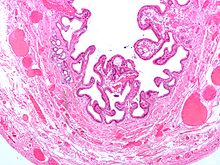

Микроснимок жёлчного пузыря при холецистите.

Холецистит (от греч. χολή — жёлчь и κύστις — пузырь) — воспаление желчного пузыря.